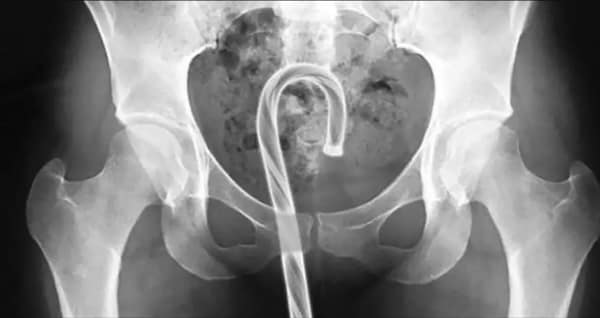

I used to think that nothing could surprise me anymore—until I stumbled upon some weird x-ray photos that made me reconsider my stance on human ingenuity (or lack thereof). Apparently, some people have a knack for getting objects lodged where they absolutely shouldn’t be. If you’ve ever wondered how not to use everyday items, these images might provide some unintended guidance.

This collection showcases 31 bizarre x-ray images that defy logic and anatomy textbooks alike. Each photo reveals unexpected objects making cameo appearances inside the human body, turning medical imaging into a gallery of the absurd. From common household items inexplicably found in unusual places to anomalies that would leave even seasoned doctors scratching their heads, these images offer a perplexing glimpse into the more “creative” side of medical emergencies. They highlight the intersection of curiosity, misadventure, and perhaps a dash of poor decision-making, all captured through the lens of radiology.